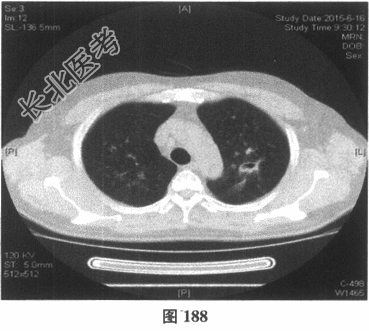

- 多项选择题4.[提示]患者应用多种抗生素治疗(第三代头孢菌素、青霉素加酶抑制剂)包括抗曲霉菌治疗无效,加用甲泼尼龙40mg静脉滴注病情好转。肺部CT检查显示病变明显改善。尿常规检查正常, 肾功能检测正常。复查肺部CT(图188~图195):示病变较前好转。Wegener肉芽肿的主要临床表现是( )